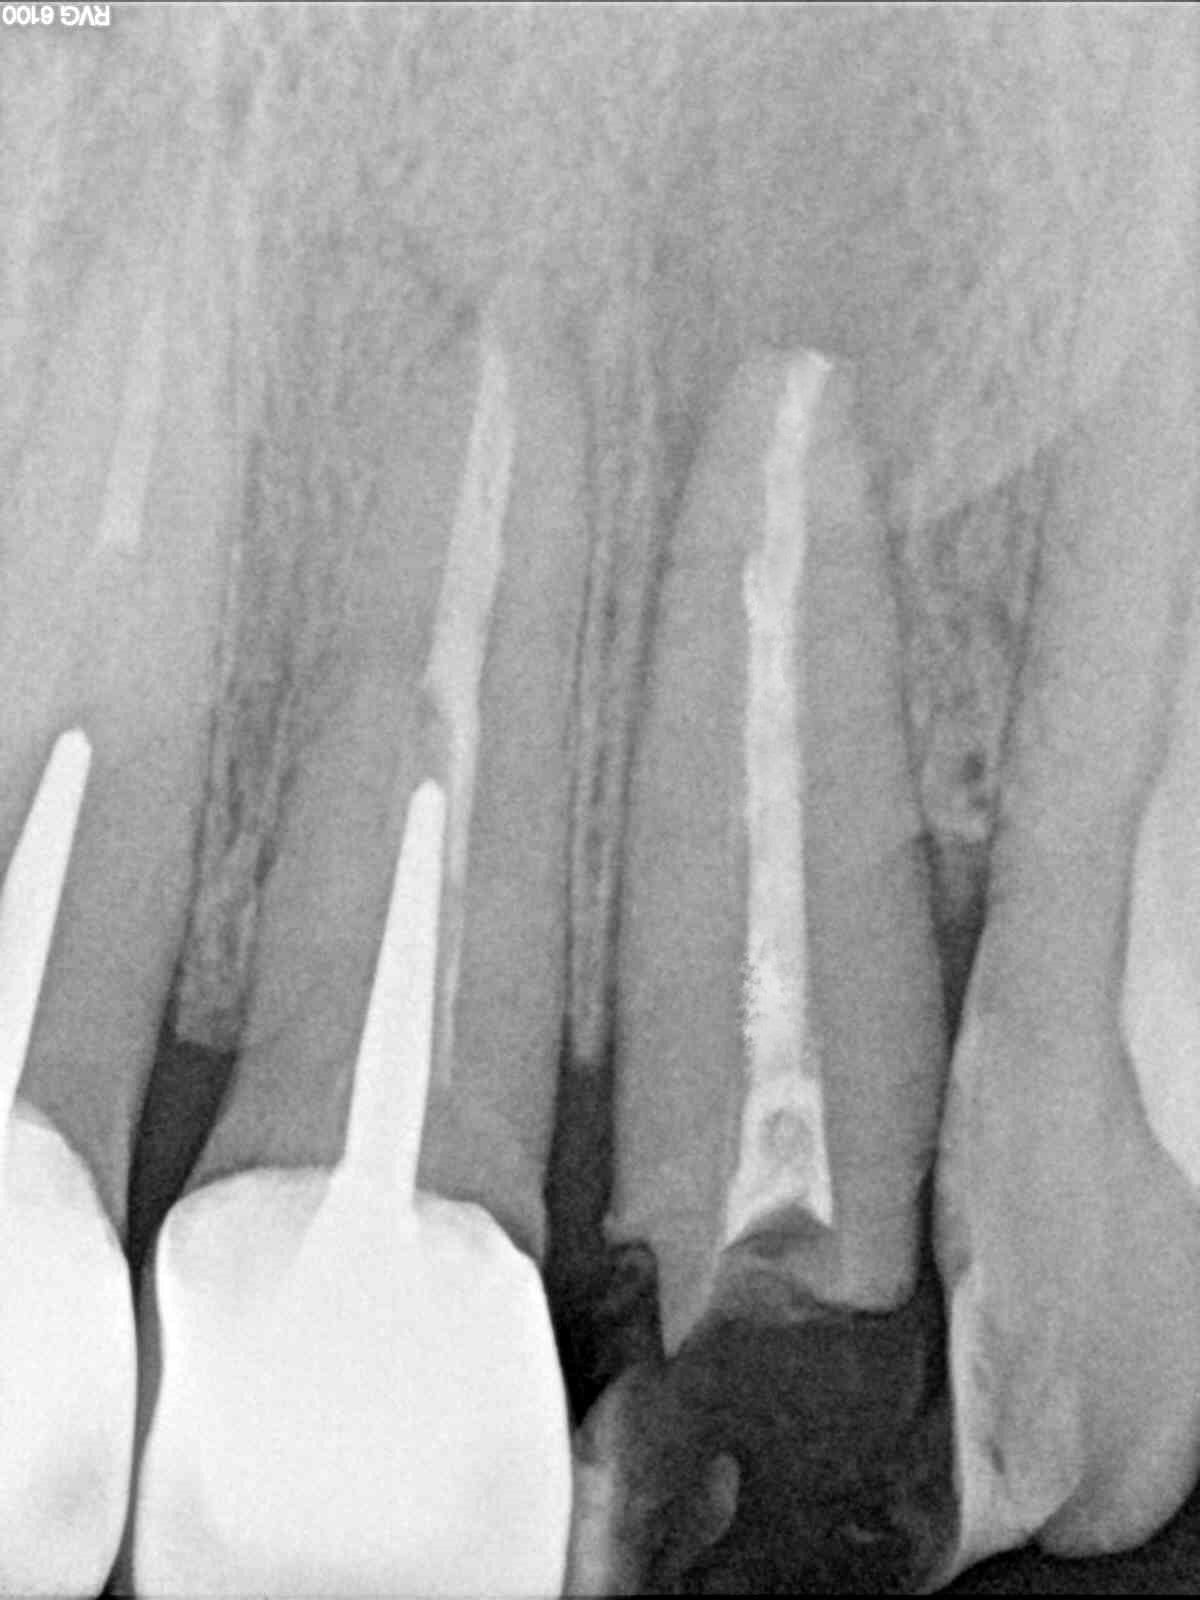

Tu vois la ligne d escalier horizontale sur tout le cliche. Mais rien n est impossible...

C’est un artefact qui se voit au niveau de la molaire aussi et surtout sur l’autre PM!

Sinon j’aurais posé un implant directement sans passer par la case départ Daryl , tu penses bien :)